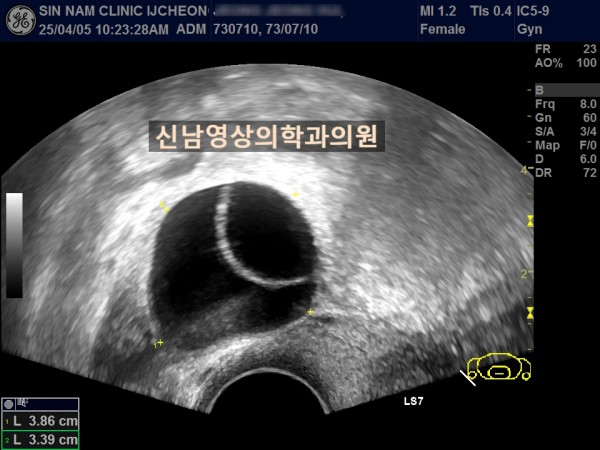

연령 : 52세

하복부 통증으로 내원하셨고, 초음파 검사상 자궁선근종과 난소낭종이 발견되었고, 난소암 혈액검사를 진행했습니다.

난소암 혈액검사 결과는 정상범위로 약간 높은 수치였기에 생리 끝나고, 다시 추적검사를 진행하기로 했지만 복통이 심해져 수술 진행했고, 수술장에서는 암의 가능성이 없는 것으로 전달 받았으나 최종 조직검사상 난소암으로 진단되었습니다.

여성들의 경우 난소 내막종에서 난소암으로 진행될 위험이 있고, 자궁선근종이 있는 분들은 난소내막종이 동반될 가능성도 높기 때문에 주기적으로 추적검사가 필요하고, 난소암 혈액검사와 초음파상 혹의 모양을 종합적으로 판단해 수술결정을 하게 됩니다.

난소낭종의 문제는 혹의 꼬이면서(염좌) 복막염으로 진행될 위험이 있다는 것입니다.

난소혹의 형태가 애매할 경우에는 생리직후에 추적검사로 형태 변화가 있는지를 관찰하는 것이 필요합니다.